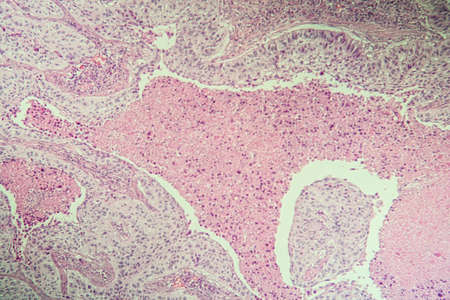

Squamous cell carcinoma diseased tissue under the microscope 100x